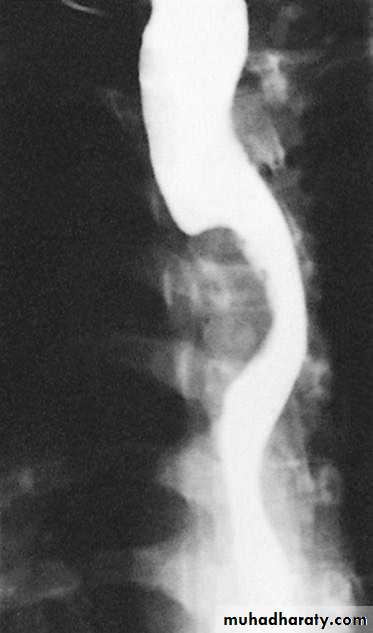

Figure2: Squamous cell carcinoma of the oesophagus producing

an irregular stricture with shouldered marginsClinical features: